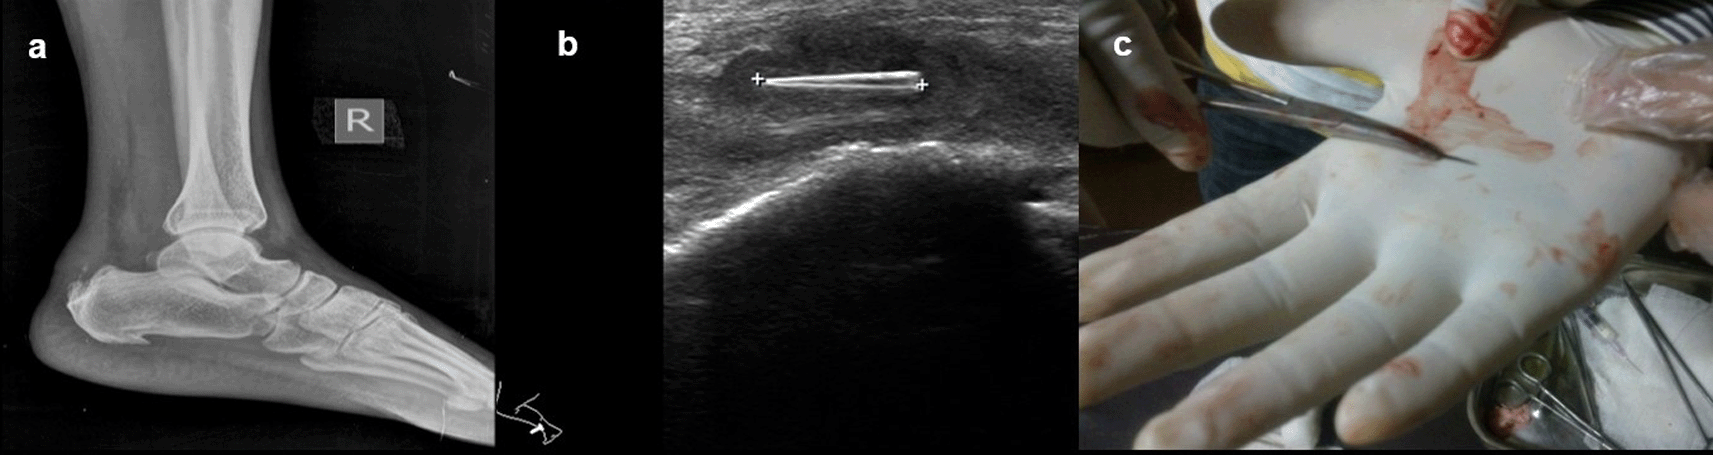

Case 7: A 40-year-old male presented with a complaint of pain in the right heel region for two months. A radiograph of the lateral view of the right foot revealed there was evidence of calcific tendinitis of the Achilles tendon with thickening of the Kager fat pad and fat stranding. USG revealed that a well-defined thorn visualized in the Achilles tendon with associated surrounding tendinitis and increased fat echogenicity. USG-guided thorn removal was performed.

On ultrasound, all foreign bodies in soft tissue are initially hyperechoic. Sonography is important for the correct localization of all kinds of soft tissue foreign bodies and the detection of non-radiopaque foreign bodies. Accurate localization can help minimize surgical exploration and can also direct the percutaneous removal of a foreign body11 (Figure 7a,b)

USG revealed that a well-defined thorn visualized in the Achilles tendon with associated changes of tendinitis (b). Thorn removed under ultrasound guidance (c).